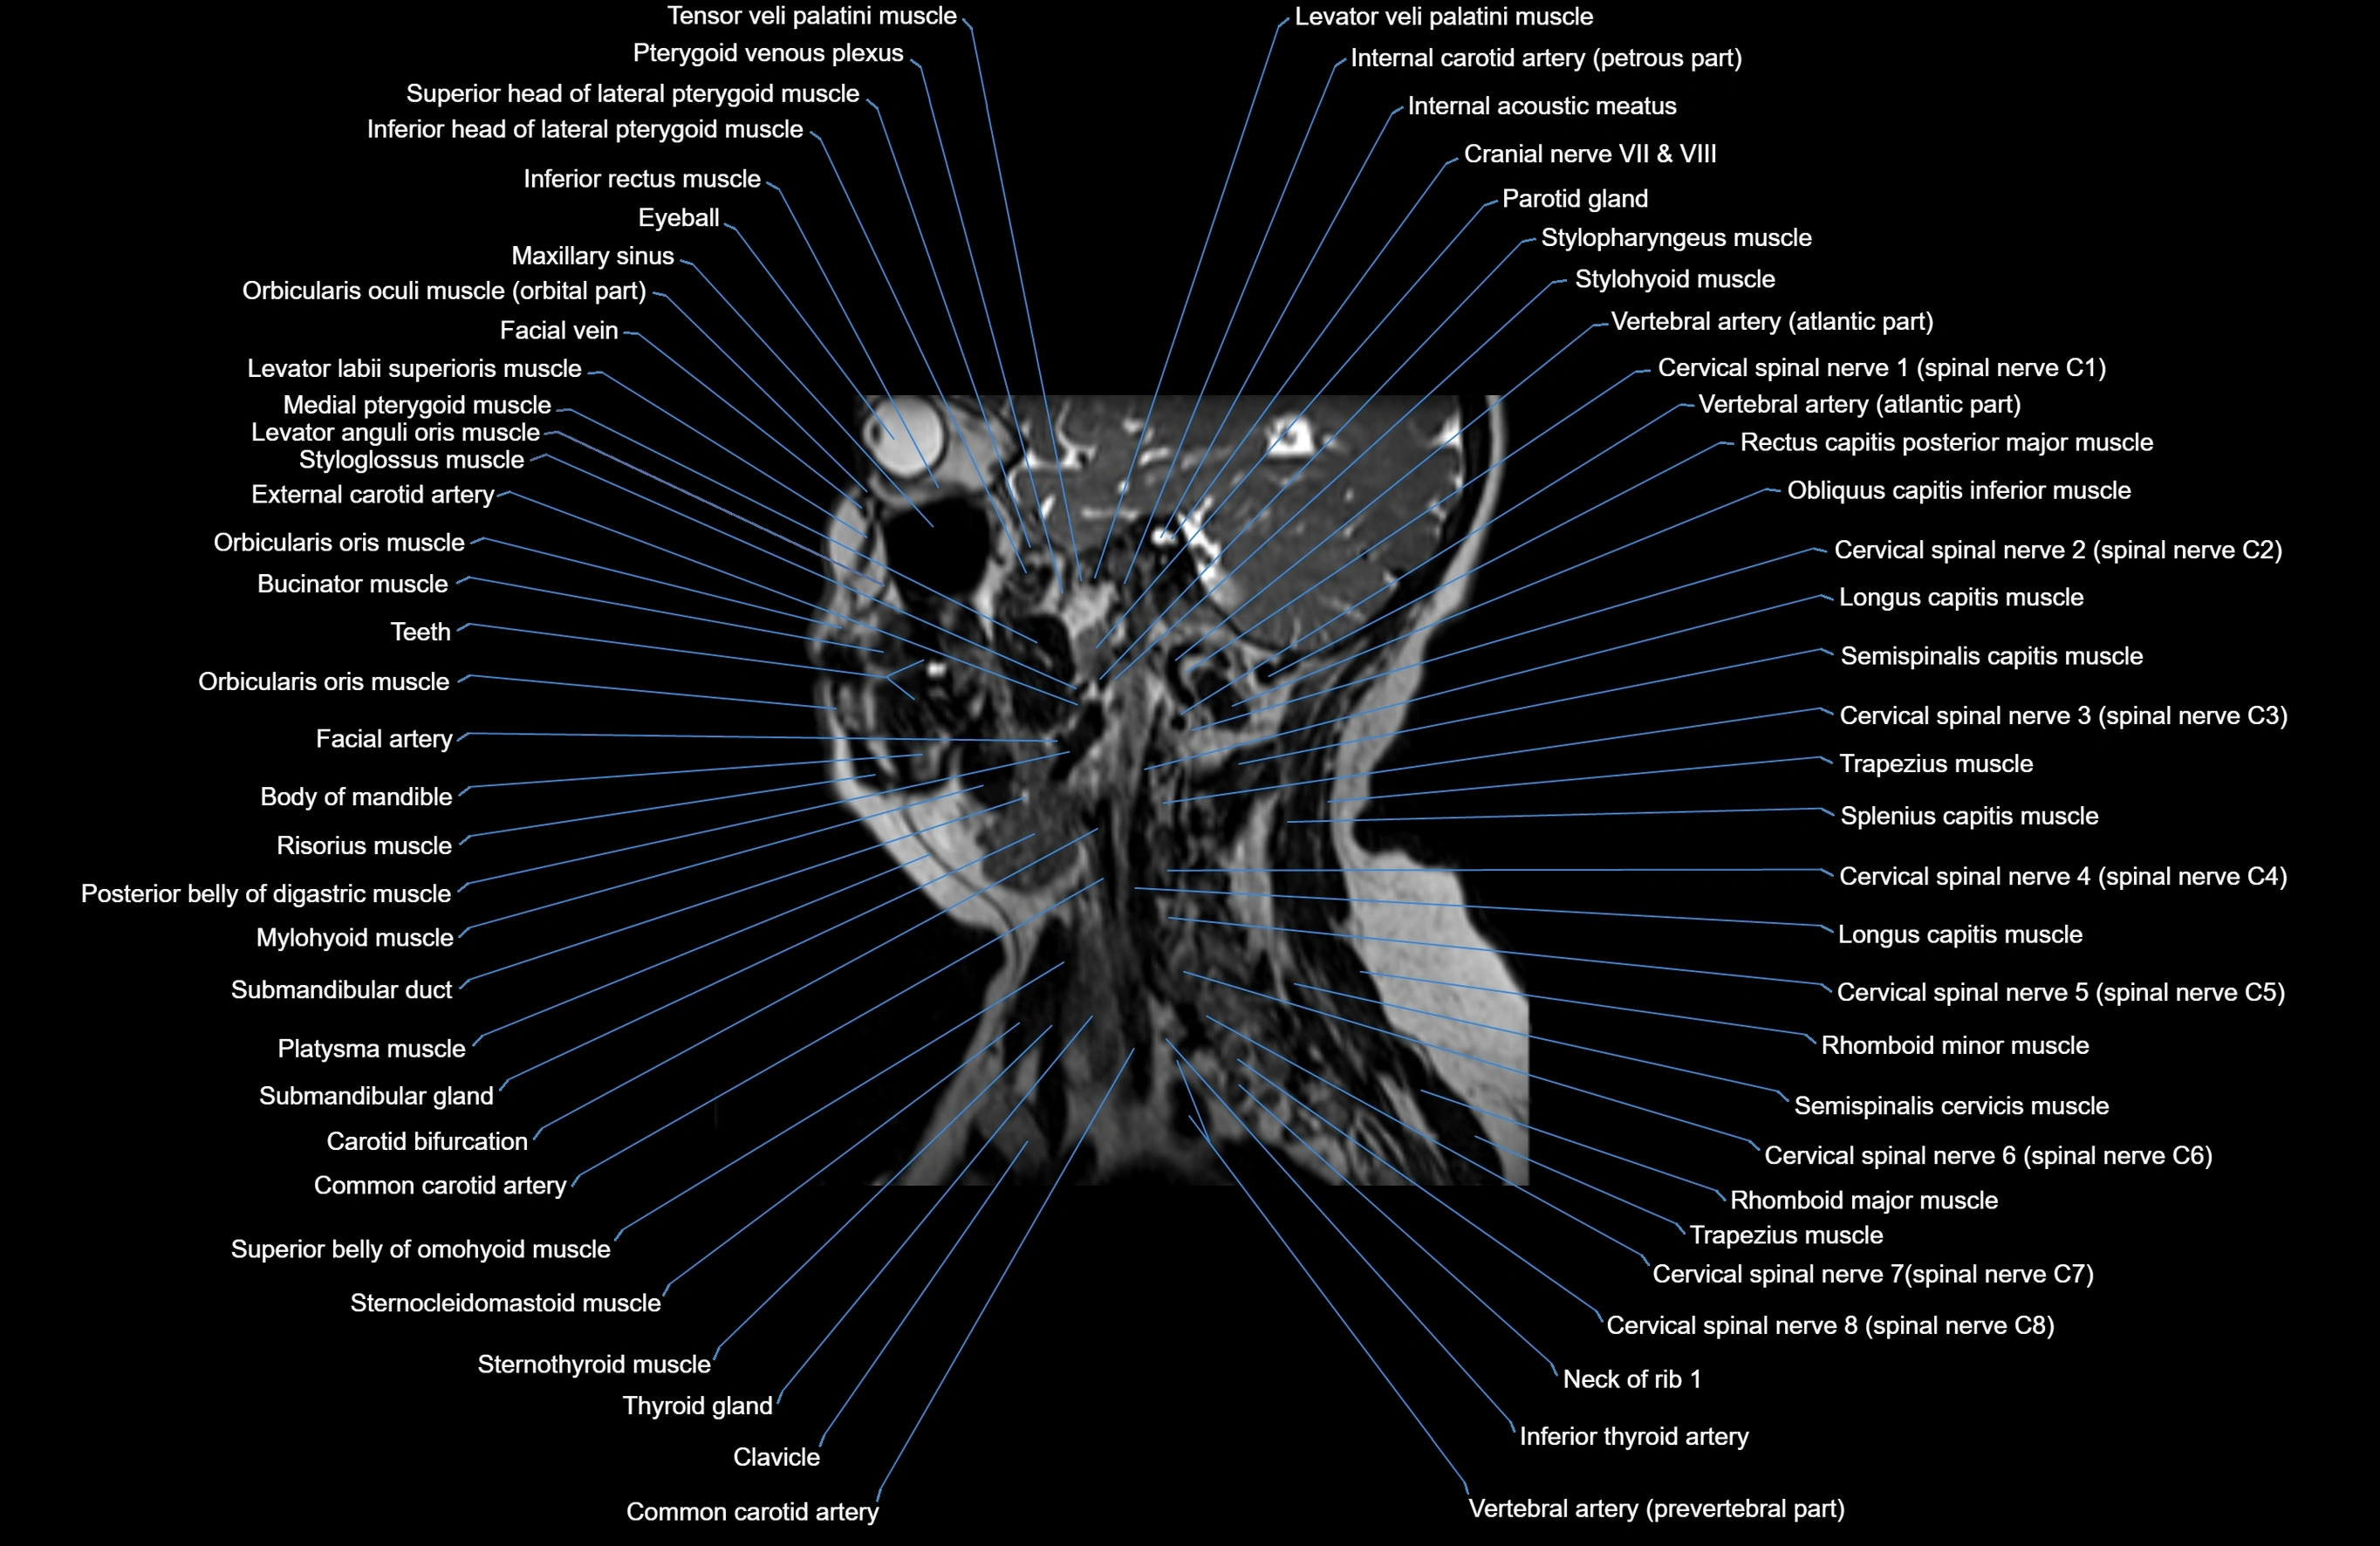

MRI images